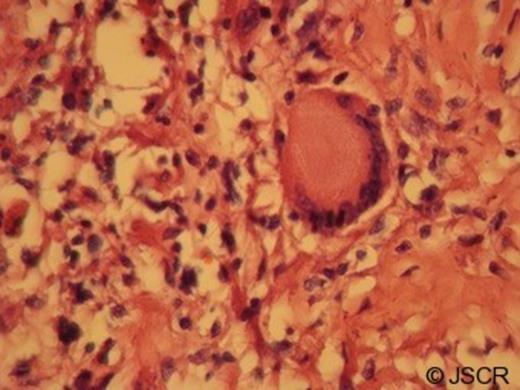

Macroscopically the ileum and caecum showed multiple caseating necrotic materials. On microscopic evaluation several caseating granulomatous inflammations composed of epithelioid histiocytes and Langhan’s giant cells were seen in the ileum, caecum and also mesenteric lymph nodes. Ziehl-Neelsen staining for Mycobacterium tuberculosis was negative. However, positivity of PCR assay for Mycobacterium tuberculosis on paraffin embedded tissue block confirmed the diagnosis.

Low power photomicrograph showing mucosal ulceration of intestinal wall with hemorrhage and collection of lymphocytes (× 100)